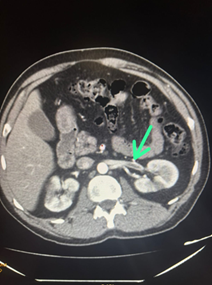

Se realizó angiotomografía de aorta total, tórax, abdomen y pelvis donde se llegó al diagnóstico de tromboembolismo pulmonar (TEP) agudo izquierdo, trombosis parcial de la vena renal izquierda (figura 5A) y signos de infarto renal bilateral (figura 5B).

Figura 5. Angiotomografía de aorta, tórax, abdomen y pelvis. A. La flecha muestra el déficit de relleno en la vena renal izquierda. B. La flecha indica el área de infarto renal izquierdo.